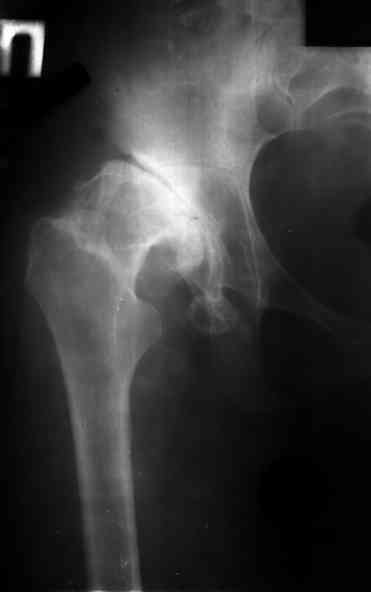

Диспластический коксартроз

Ув. коллеги, женщина, 37 лет, имеет диспластический коксартроз.

Сомневается в положительном результате от эндопротезирования, но хочет оперироваться. Что порекомендуете?